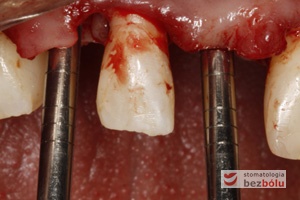

Ocena pozycji implantów w wymiarze strzałkowym - piny do oceny równoległości wprowadzone do łoży implantów - widok okluzyjny

Ocena pozycji implantów w wymiarze strzałkowym – piny do oceny równoległości wprowadzone do łoży implantów – widok okluzyjny